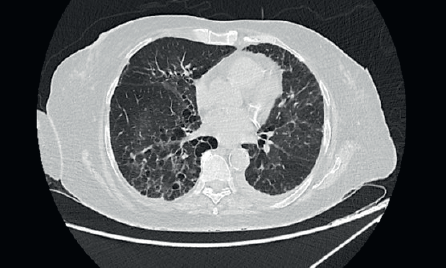

A 67-year-old post-menopausal lady was diagnosed to have metastatic hormone positive breast cancer in February 2019. Her imaging showed multiple bony metastases with few bilateral subpleural metastases (<1 cm). She underwent open reduction and internal fixation for a pathological fracture of her right neck of femur. Biopsy of the breast lump showed an infiltrating ductal carcinoma grade 1, Estrogen receptor (ER) + (Allred 8/8), progesterone receptor+ (PR+) and HER2 negative. She was a well-controlled hypertensive and had a background of bronchiectasis (Figure 1) for which she was asymptomatic. Her bronchiectasis was first diagnosed in 2 years prior to the current diagnosis of breast cancer, when she presented to another hospital was a probable infective exacerbation of underlying lung disease. She had no prior history of necrotising pneumonia in childhood or tuberculosis or features of ciliary dyskinesias/cystic fibrosis. There was no clinical or serological evidence of autoimmune disease (acute inflammatory markers were, however, elevated due to inflammatory, fumigating breast carcinoma). Acute infective aetiologies were also ruled out, with multiple blood and sputum cultures for bacteria, mycobacteria and fungi yielding no growth. Polymerase chain reaction (PCR) for viruses and mycobacteria was also negative. There was no evidence of immunocompromise other than underlying malignancy which was diagnosed subsequently in Feb 2019.

Figure 1. High-resolution CT thorax of the patient prior to initiation of CDK 4/6 inhibitor (Palbociclib).